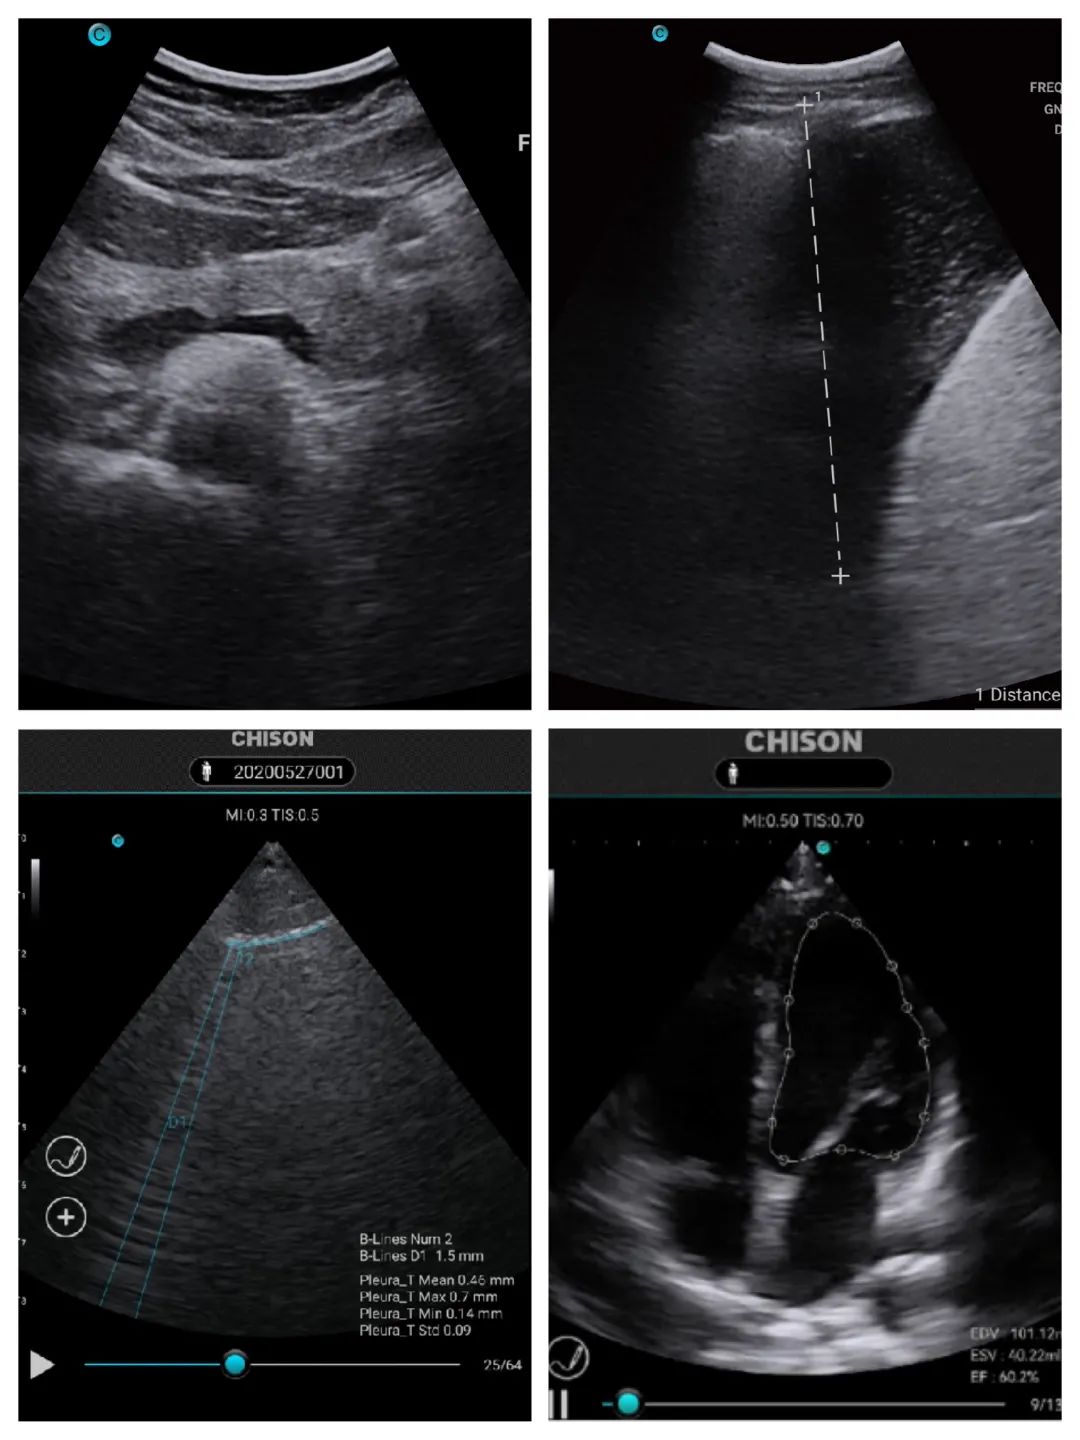

In the process of air-ground integration rescue, the helicopter undertakes the dual tasks of "rescue" and "transfer". A hand-held ultrasound machine is an ideal first-aid tool to be equipped on the helicopter.SonoEye can quickly complete the basic physical assessment of patients by well-trained first-aid personnel in such a limited space, and help to save plenty of time for the treatment as much as possible.

Images and vital data of the patient will be transmitted in real time to the central hospital on the ground by this integrated 5G Air-ground rescue system. In this way, the whole treatment process will be well guaranteed in advance. Under some extreme conditions, every minute is racing with life.

performance. SonoEye 's fast processing platform brings brilliant

ultrasound image quality, which is a milestone for CHISON.Moreover, SonoEye can take you to experience digital

intelligent ultrasound, bringing you simple operation and accurate